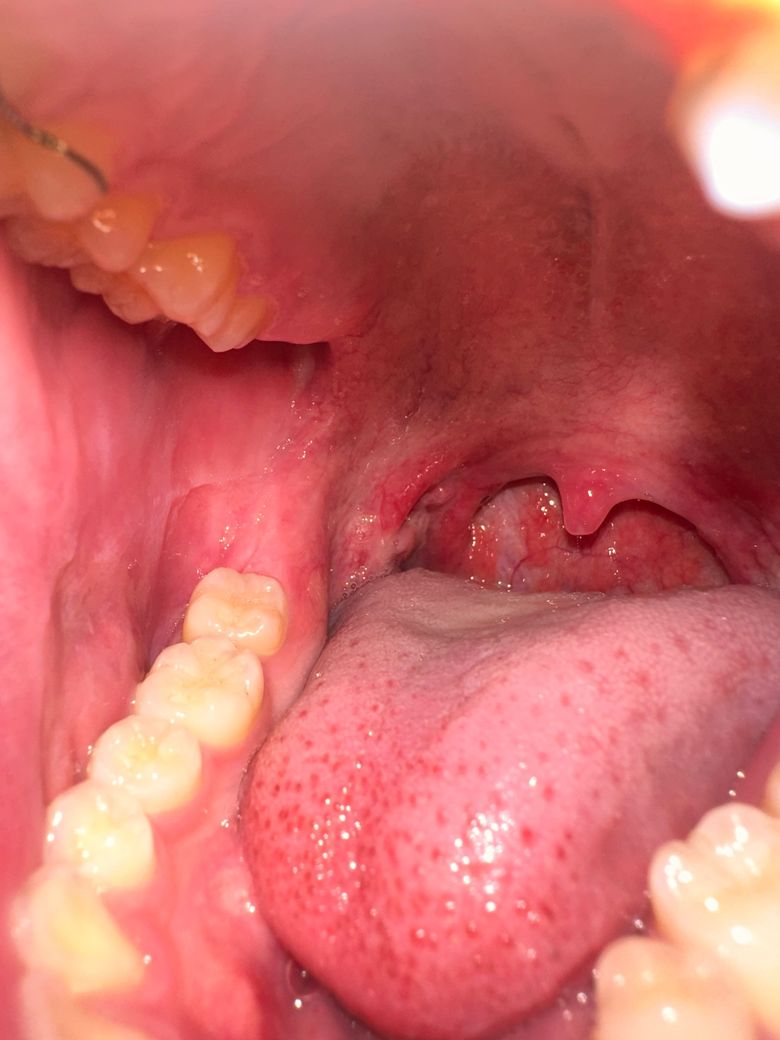

편도완전절제후에도 편도가 남아있는것 같아요

편도완전절제 수술을 받고 3주정도 지나서 곱도 다 떨어지고 붓기도 줄어서 제대로 확인해봤는데 편도 부분이 엄청 울퉁불퉁하고 아직 편도가 남아있는것 같아서요 혹시 수술이 제대로 안된걸까요? 그리고 편도결석이 또 생길수도 있을까요?

• 1번 째 사진

편도완전절제 후 3주 시점에 보이는 울퉁불퉁한 모습은 대부분 정상적인 회복 과정입니다. 수술 시 편도 조직 자체는 제거되지만, 그 자리에 남는 편도와(fossa)와 흉터 조직, 육아조직, 림프조직 잔여물이 불규칙하게 보여 편도가 남아 있는 것처럼 느껴질 수 있습니다. 이는 수술이 불완전해서라기보다 상처가 아물어 가는 자연스러운 소견인 경우가 많습니다.

편도결석은 일반적으로 편도 크립트가 남아 있을 때 생기므로, 완전절제 후에는 재발 가능성이 매우 낮습니다. 다만 극히 드물게 주변 림프조직이나 흉터 요철에 음식물 찌꺼기가 끼어 불편감을 느낄 수는 있으나, 전형적인 편도결석과는 다릅니다. 통증, 악취, 반복되는 염증이 동반되지 않는다면 경과 관찰이 원칙이며, 의심될 경우 수술한 이비인후과에서 직접 확인받는 것이 가장 정확합니다.

올려주신 사진으로는 편도 수술 부위를 명확히 확인하긴 어렵습니다.

편도 조직이 남았을지 걱정이 되신다면 다시 이비인후과를 방문하여 진찰을 받아 보실 것을 권합니다.